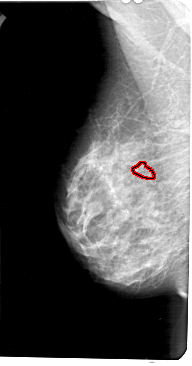

A_1213_1.LEFT_MLO

LEFT_MLO LINES 5476 PIXELS_PER_LINE 2866 BITS_PER_PIXEL 12 RESOLUTION 43.5 OVERLAY

FILE: A_1213_1.LEFT_MLO.OVERLAY

TOTAL_ABNORMALITIES 1

ABNORMALITY 1

LESION_TYPE CALCIFICATION TYPE PLEOMORPHIC DISTRIBUTION CLUSTERED

ASSESSMENT 4

SUBTLETY 4

PATHOLOGY MALIGNANT

TOTAL_OUTLINES 1

BOUNDARY